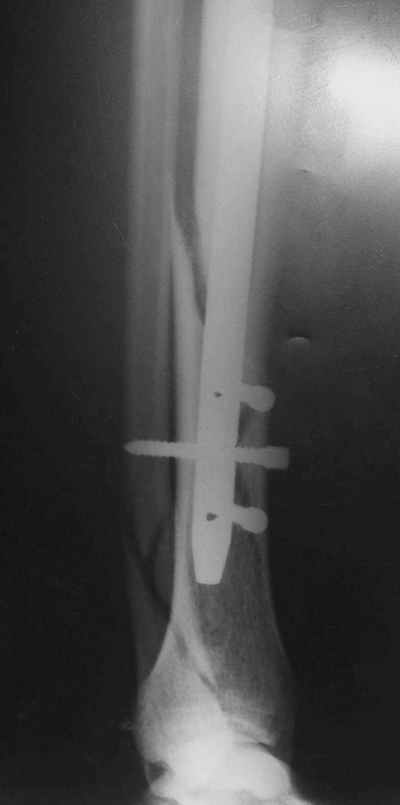

В 2002 г. была у нас больная с ложным суставом бедра и остеомиелитом (как оказалось), после удаления пластины. Гвоздь с блокированием.

Потекло через месяц - открылось 2 свища по старому рубцу от давно удаленной пластины. На фоне гноя раза три завинчивал обратно винты, которые вылезали латерально, прямо через свищ. Потом таки провел дополнительно винты мимо гвоздя, и убрал вверху статический винт. Острый гнойный процесс стих, свищи мыла она дома дважды в день водным хлоргексидином, ходила с возрастающей нагрузкой, а к 10 мес. и свищи закрылись, и срослось. Итоговые снимки от 18 апреля 2003 г. прилагаю.

Отправитель: Alexander Chelnokov 21 Январь 2005, 21:31

Перелом спиральный, то есть низкоэнергетический, так что со сращением дело обстоит уже неплохо, лишь бы "костоеда" не развилась. Отломки выглядят уже стабилизированными костной мозолью, так что довводить винты, наверно, уже незачем. Разве что при клинической оценке подвижность еще есть - тогда можно для стабилизации наложить простейший аппарат, не опасаясь контакта его элементов с гвоздем, поскольку места в дистальном метафизе оставлено более чем достаточно.